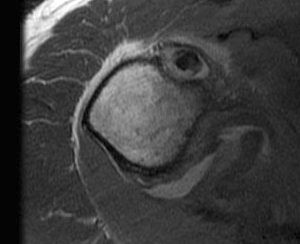

Sagittal MRI demonstrating severe LHB tendinopathy